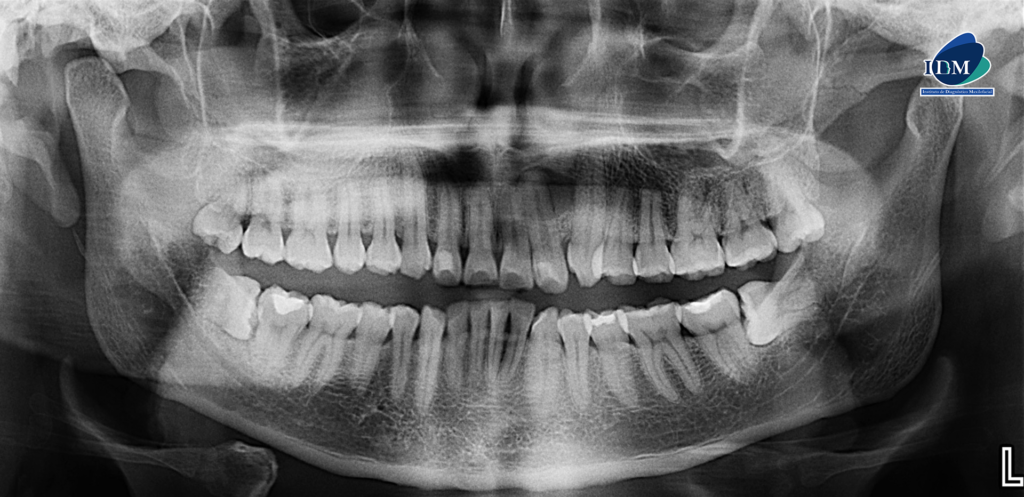

Paciente masculino de 33 años acude para una revisión general. A la evaluación de la radiografía panorámica se observa la neumatización de ambos senos maxilares, múltiples restauraciones y piezas 38 y 48 impactadas en posición horizontal. Asimismo, se observa la pieza 22 con material restaurador en cara libre y una imagen radiolucida corticalizada de forma redondeada que se proyecta sobre la porción radicular de la misma que se extiende hasta mesial de la pieza 23.

Radiografia Panorámica